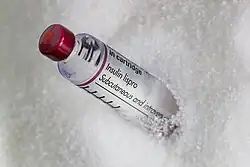

Insulin lispro

Insulin lispro, marketed under the brand name Humalog among others, is a modified form of medical insulin used to treat both type 1 and type 2 diabetes.[17] It is administered subcutaneously through injection or an insulin pump.[18][19] The effects typically begin within 30 minutes and last for about 5 hours.[17] Sometimes, a longer-acting insulin, such as insulin NPH, is also used.[20]

Common side effects include low blood sugar, while more serious side effects may include low blood potassium.[21] It is generally considered safe for use during pregnancy and breastfeeding.[22][23] It functions similarly to human insulin by increasing glucose uptake in tissues and reducing the amount of glucose produced by the liver in gluconeogenesis.[24]

Insulin lispro was first approved for use in the United States in 1996.[18][25][26] It is a synthetic analogue of human insulin, created by swapping two amino acids.[27] In 2022, it ranked as the 70th most commonly prescribed medication in the United States, with over 9 million prescriptions.[28][29] Insulin lispro is available under a generic label from Lilly.[30]